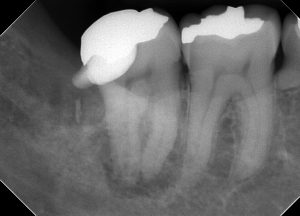

レントゲンを見てみよう。

(術前のレントゲン、CT)

半埋伏智歯(半分歯茎の中に埋まっている親知らず)の影響で、右下7番の遠心にう蝕があったであろうことが分かる。

この場所は、親知らずが無ければ、本来虫歯ができるはずがない場所だ。

このようなことがあるので、半埋伏智歯は早めに抜いておいた方が良いのかもしれない。

一つ言えることは、この場所に虫歯ができると「治療が非常に難しくなる」ということである。

理由は簡単、見えにくいからだ。

現に過去の虫歯治療の状態は、問題だらけだ。

・虫歯も取りきれていない

・裏層したセメントは大きくはみ出している

・修復物の適合も全くあっていない

見えない場所を、盲目的に、感覚頼りに治療したのだろう。

そして、結果的に神経が死んでしまい、かなり広範囲に骨が溶けてしまっている。